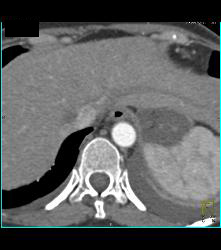

Diagnosis

Intramural Hematoma